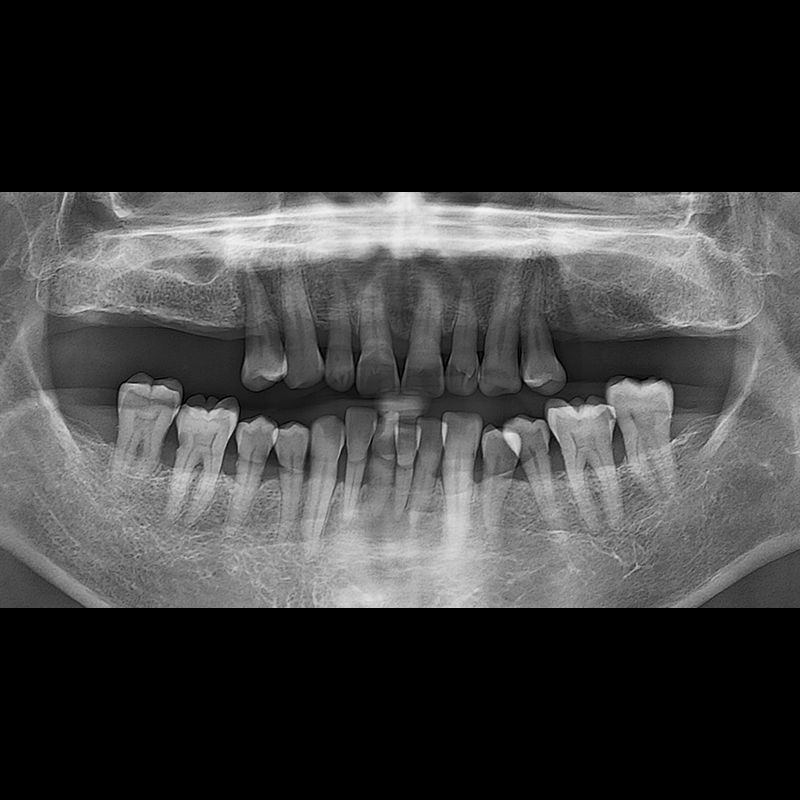

BEFORE AFTER

임플란트 전후사진 2025.05.30

결손된 치아 부분과 살리기 힘든 치아 위치에 임플란트를 식립하였습니다.